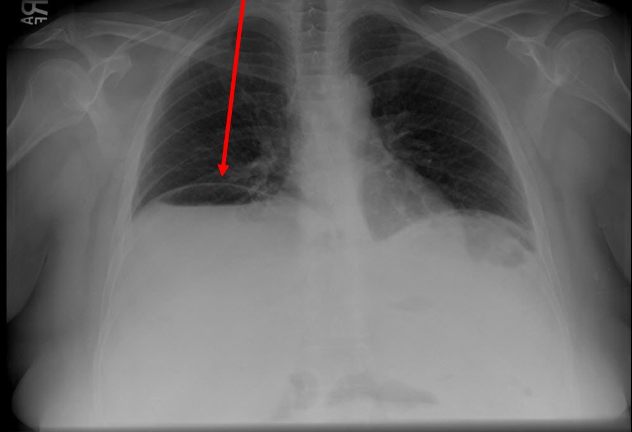

Pathology?

Free air under diaphragm